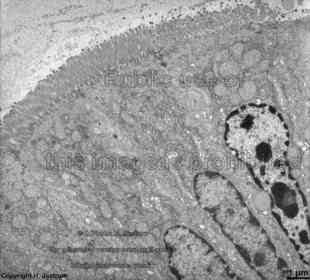

Goblet cell

A : secretory granules containig mucous B : Nucleus C : rER D : Enterocyte